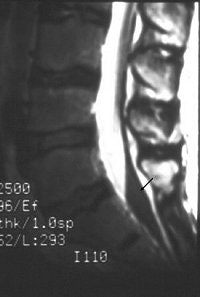

Finally, MRI can be used to study dural tears resulting from spinal fractures. Dural tears may result in entrapment of nerve roots between laminar fragments (images H-J above). Such dural tears may delay, if not preclude, recovery, El-Khoury said. MRI has been found to be 100% sensitive and 74% accurate for diagnosing dural tears as a result of burst fracture, he added.

![]() ![]() ![]() |